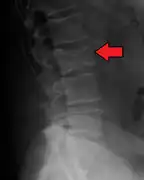

The diagnostic examination of a person with suspected multiple myeloma typically includes a skeletal survey. This is a series of X-rays of the skull, axial skeleton, and proximal long bones. Myeloma activity sometimes appears as "lytic lesions" (with local disappearance of normal bone due to resorption). And on the skull X-ray as "punched-out lesions" (pepper-pot skull). Lesions may also be sclerotic, which is seen as radiodense.[47] Overall, the radiodensity of myeloma is between −30 and 120 Hounsfield units (HU).[48] Magnetic resonance imaging is more sensitive than simple X-rays in the detection of lytic lesions, and may supersede a skeletal survey, especially when vertebral disease is suspected. Occasionally, a CT scan is performed to measure the size of soft-tissue plasmacytomas. Bone scans are typically not of any additional value in the workup of people with myeloma (no new bone formation; lytic lesions not well visualized on bone scan).

X-ray of the forearm, with lytic lesions

Pathological fracture of the lumbar spine due to multiple myeloma